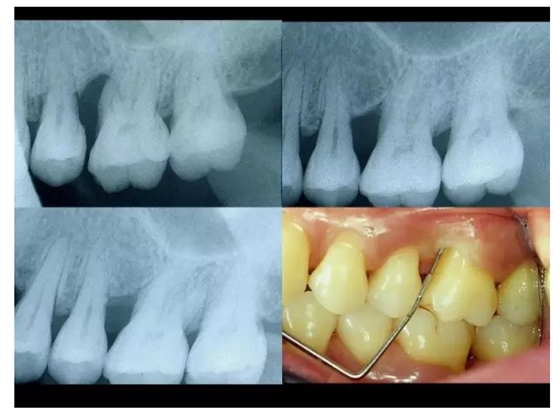

【牙科知識(shí)】牙周病相關(guān)手術(shù)圖解,非醫(yī)學(xué)專業(yè)勿點(diǎn)